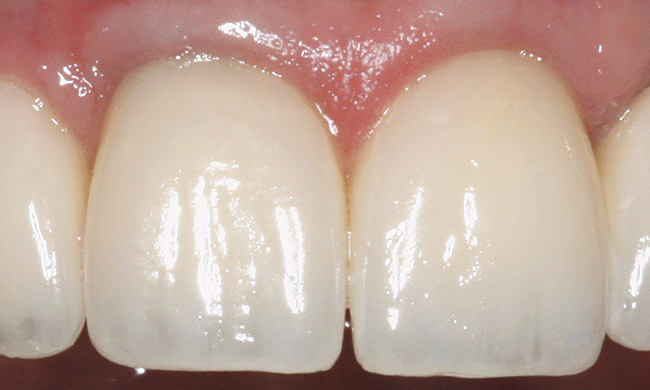

Figure 16  ENDODONTIC AND ESTHETIC PARAMETERS  Gingival symmetry is defined as an imaginary line that should be collinear connecting the central incisors and canines. The gingival margin of the lateral incisor should be even with or coronal to this line by a maximum of 3 mm.

Figure 16